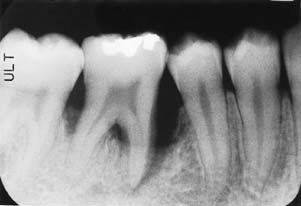

Рентгенологический снимок – резорбция челюсти

Резорбция челюсти